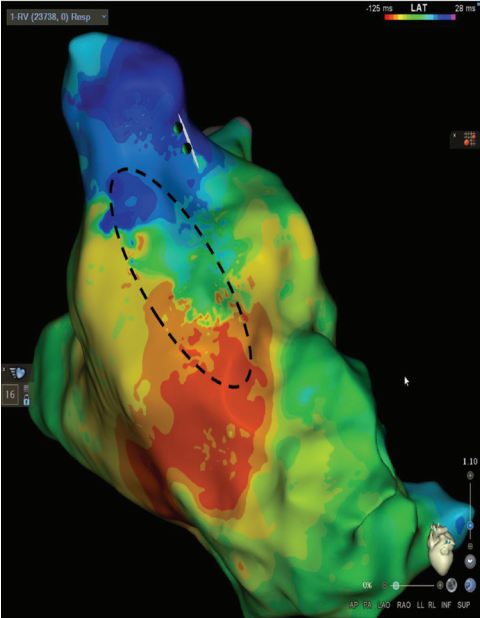

Isochronal Late Activation Mapping

The same RV pacing substrate map can be evaluated using isochronal late activation mapping (ILAM). This method identifies slowly conducting areas termed deceleration zones, which are defined as 3 or more isochrones within a 1-cm area of myocardium. In this case, a deceleration zone is located within the same SCAI seen in Figure 1 highlighted by the dashed circle in Figure 2. The use of ILAM in repaired TOF is not as well established as SCAI identification, although one recent study demonstrated a 90% correlation between identified SCAIs and ILAM deceleration zones in repaired TOF.4,5 One simple way to recognize both a SCAI and an ILAM deceleration zone is to evaluate the 1-cm area for ILAM through the anatomic isthmus identified by voltage mapping. Each isochrone can then be set to 10 ms, so if there are 3 or more isochrones through the isthmus establishing it as a deceleration zone, it can be immediately determined that the SCAI is <0.5 m/s (ie, 1 cm/30 ms = 0.33 m/s).